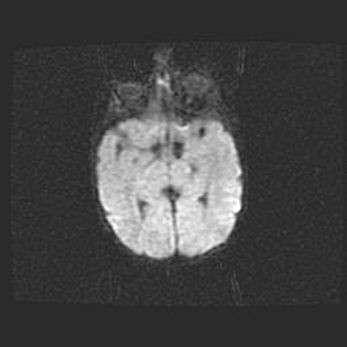

Церебральная ишемия II.

Возраст: 7 дней

Вес: 3350 г

Пол: женский

Окружность головы: 35 см

Срок гестации: 39 недель

Ишемия головного мозга – это состояние, которое развивается в ответ на кислородное голодание вследствие недостаточного мозгового кровообращения. У новорожденных она является следствием дефицита кислорода, что ведет к метаболическим расстройствам различной степени тяжести в тканях головного мозга, в том числе к развитию коагуляционных некрозов и гибели нейронов.